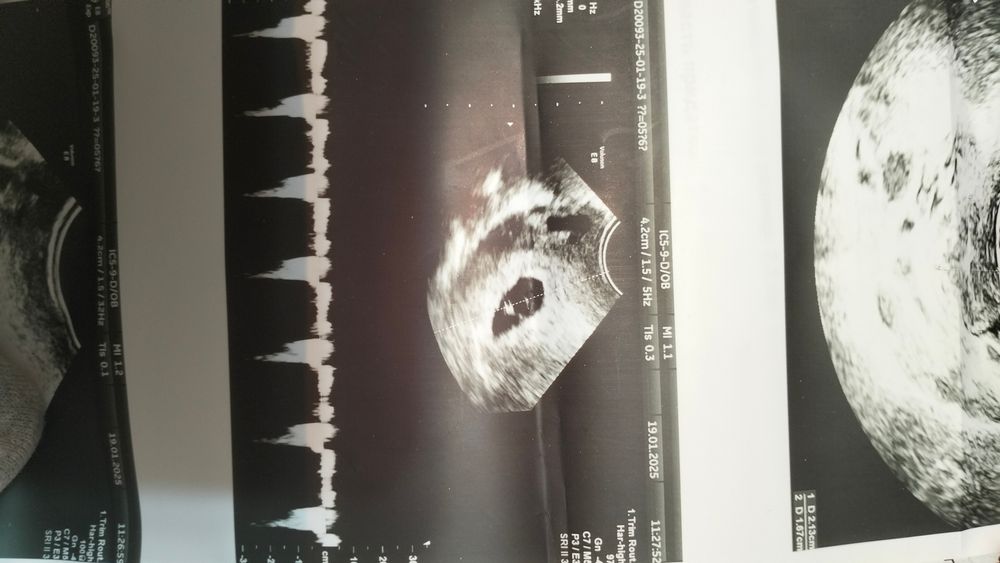

Здравствуйте! Была на УЗИ . Почти 6 недель. И врач сказала,что похоже на двойню,начала показывать,а я то ничего не вижу и не понимаю. Сказала придти через 2 недели повторно. Посмотрите, пожалуйста, может она ошиблась?

Похоже. Но ответ вам даст только узи в динамики.

Я, конечно, тоже не разбираюсь, но похоже на 2 колечка 😉🤗